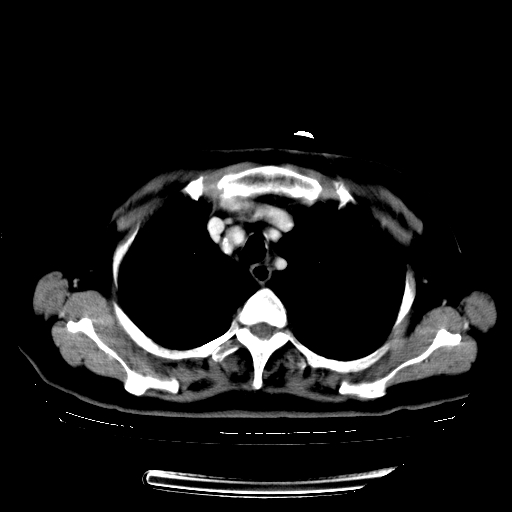

女,70岁,咳嗽、咳痰一个月,低热一周。

1.左上肺结核,部分纤维化。右肺中下叶部分肺不张,内见液化、坏死及点状钙化,右中下叶支气管壁增厚、管腔狭窄,见多个点状钙化,结合临床考虑支气管内膜结核,建议痰检查抗酸杆菌并参考血沉。两肺多个小圆点状高密度灶,境界模糊,多考虑结核肺内播散。但本人年龄较大首先应支气管镜检以除外右肺癌。

2.胸主动脉夹层。